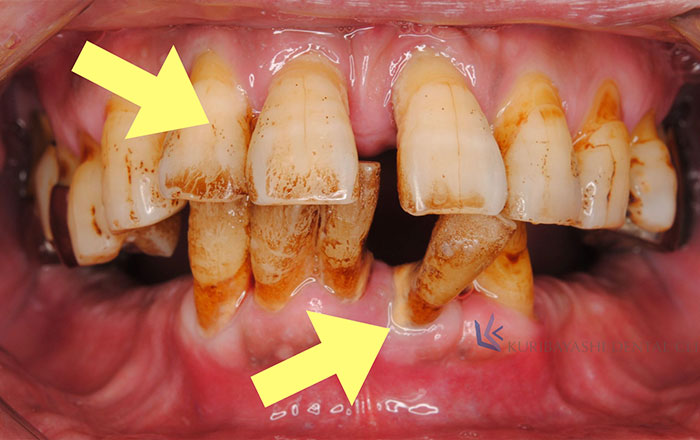

1)歯への悪影響

・歯の磨耗によって歯がしみる(知覚過敏)

・歯が欠ける・歯が割れて、噛むと痛い・噛み合わせが深くなり、被せ物が取れやすくなる

など、歯への悪影響として最終的に歯にヒビが入る、歯が欠ける、割れるといった症状があります。

2)骨への悪影響

・歯周病がより悪化しやすくなる・歯周病で既に骨が破壊されている人は、さらに進行する